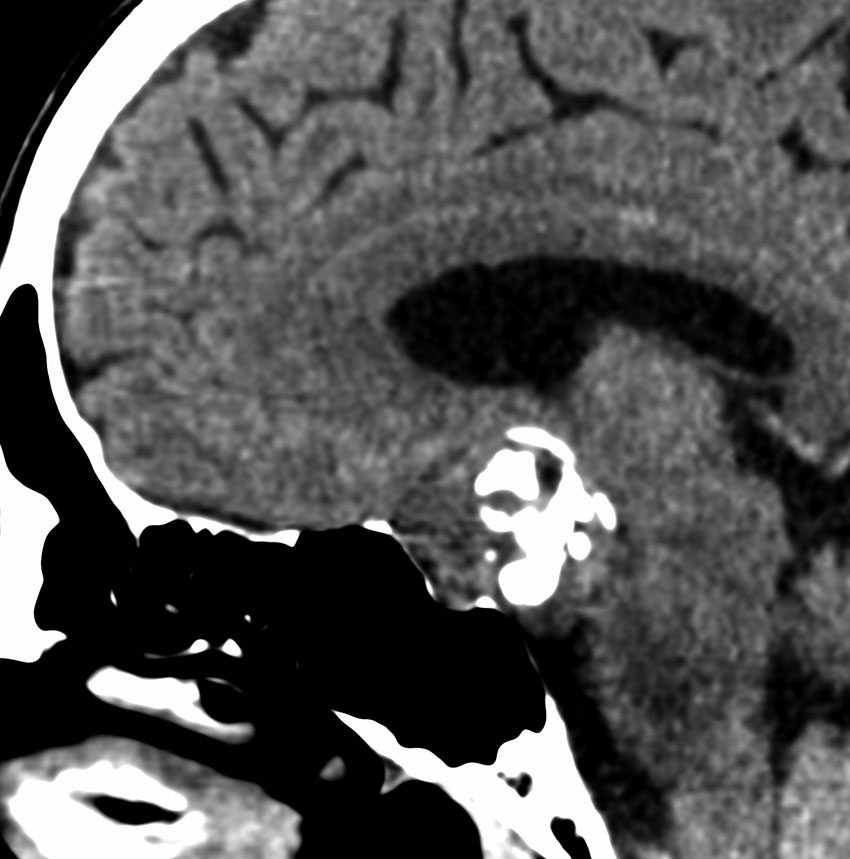

思春期の女の子にできた小脳腫瘍です。とても大きく見えますがほとんどが水たまり(のう胞といいます)。第4脳室が腫瘍で圧迫されて閉塞性水頭症になりました。のう胞の中に出血がありますが毛様細胞性星細胞腫では腫瘍内出血をしばしば見ます。右の写真で脳室が大きくなっています。こんなに大きいのに小脳症状は全くなくて,頭痛と嘔吐が症状でした。

赤で塗ったところだけが毛様細胞性星細胞腫です。これを取れば治ります。簡単な手術ですし後遺症も残りません。